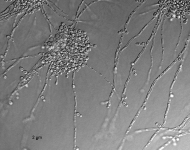

| Species Name: | Candida subhashii |

| Taxonomy: | FUNGI Ascomycota, Saccharomycetes, Saccharomycetales, Debaryomycetaceae |

| Characters: | HUMAN/ ANIMAL PATHOGEN peritonitis in patient on CAPD - Adam H, Groenewald M, Mohan M, Richardson S, et al, Med Mycol 2008 // MOLECULAR SYSTEMATICS BLAST match no sequence match with ITS & D1D2 sequences - fide UAMH // MOLECULAR SYSTEMATICS mitochondrial genome features - Fricova D, Valach M, Farkas Z, Pfeiffer I, Kucsera J, Tomaska, L, Nosek J, Microbiology 156:2153-2163, 2010 (Click for publications citing UAMH 10744) |